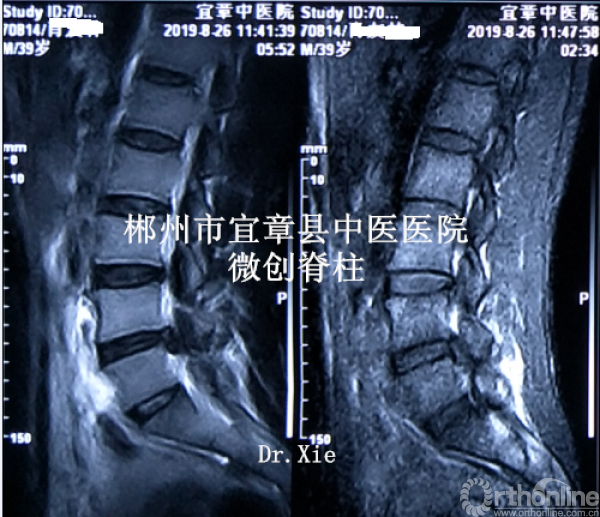

病程:腰痛伴左下肢放射痛5年,加重5天入院,入院诊断:L4/5椎间盘脱出伴坐骨神经痛。

MRI、CT影像学表现:

既往体健。专科情况:L4/5稍有压痛,左臀部致左下肢伴有明显放射胀痛感,以左小腿前外侧为明显;左侧直腿抬高试验(+),左侧踇背伸肌肌力IV级,左下肢伴有明显跛行,左侧膝反射减弱,余(-)。